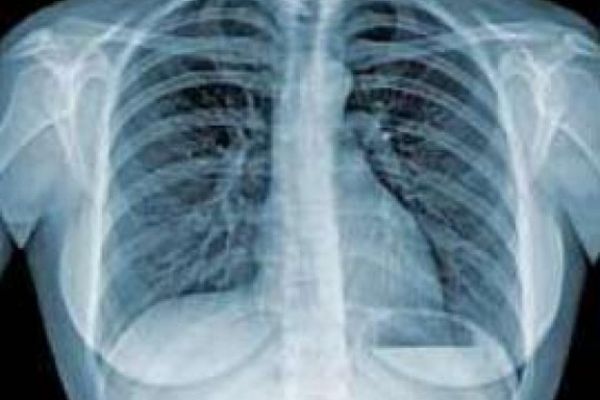

Фотоілюстрація з мережі Інтернет

Туберкульоз – широко поширене в світі інфекційне захворювання, яке викликається мікобактеріями туберкульозу. Найчастіше туберкульоз вражає легені, рідше – зачіпає інші органи і системи.